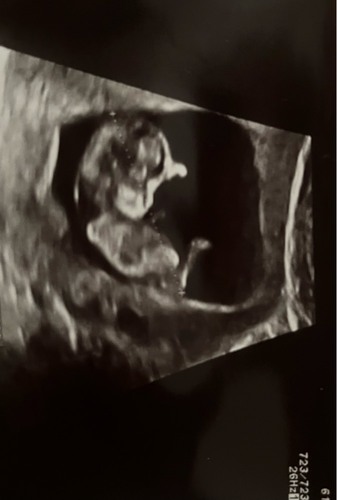

Aangezien de vorige gesloten is, bij deze nog een keer de foto. Met precies 12 weken! Ben benieuwd 😊

Ik zie alleen een hele overduidelijke nub goed hoor dus bestudeer ze niet zo lang en goed met bewerken enzo als nubster🤭

Wat ik wel doe is dat ik kijk naar nub én skull theorie. Daarmee samen kom ik bij jou uit op een meisje💗

Je laatste foto is dan weer wat verwarrend, maar dat kan ook de navelstreng zijn aangezien we de hoek niet goed kunnen zien waarin de foto genomen is🙃

Is de jongensstand nub foto van jezelf waar je het over hebt die met 11+6 de foto in profiel? Als het namelijk die is is het wel echt een meisjesnub..🌺

Als je de laatste bedoelt klopt, daar zag ik een hele duidelijke meisjes nub maaaaaaar daar was ik 10+5 (vooruitgezet naar 11 die dag) dus niet betrouwbaar nog🤭 vandaar dat ik die hier ook niet gedeeld heb. wij hebben met 14 week een geslachtsecho. Dus geen 13 weken echo.